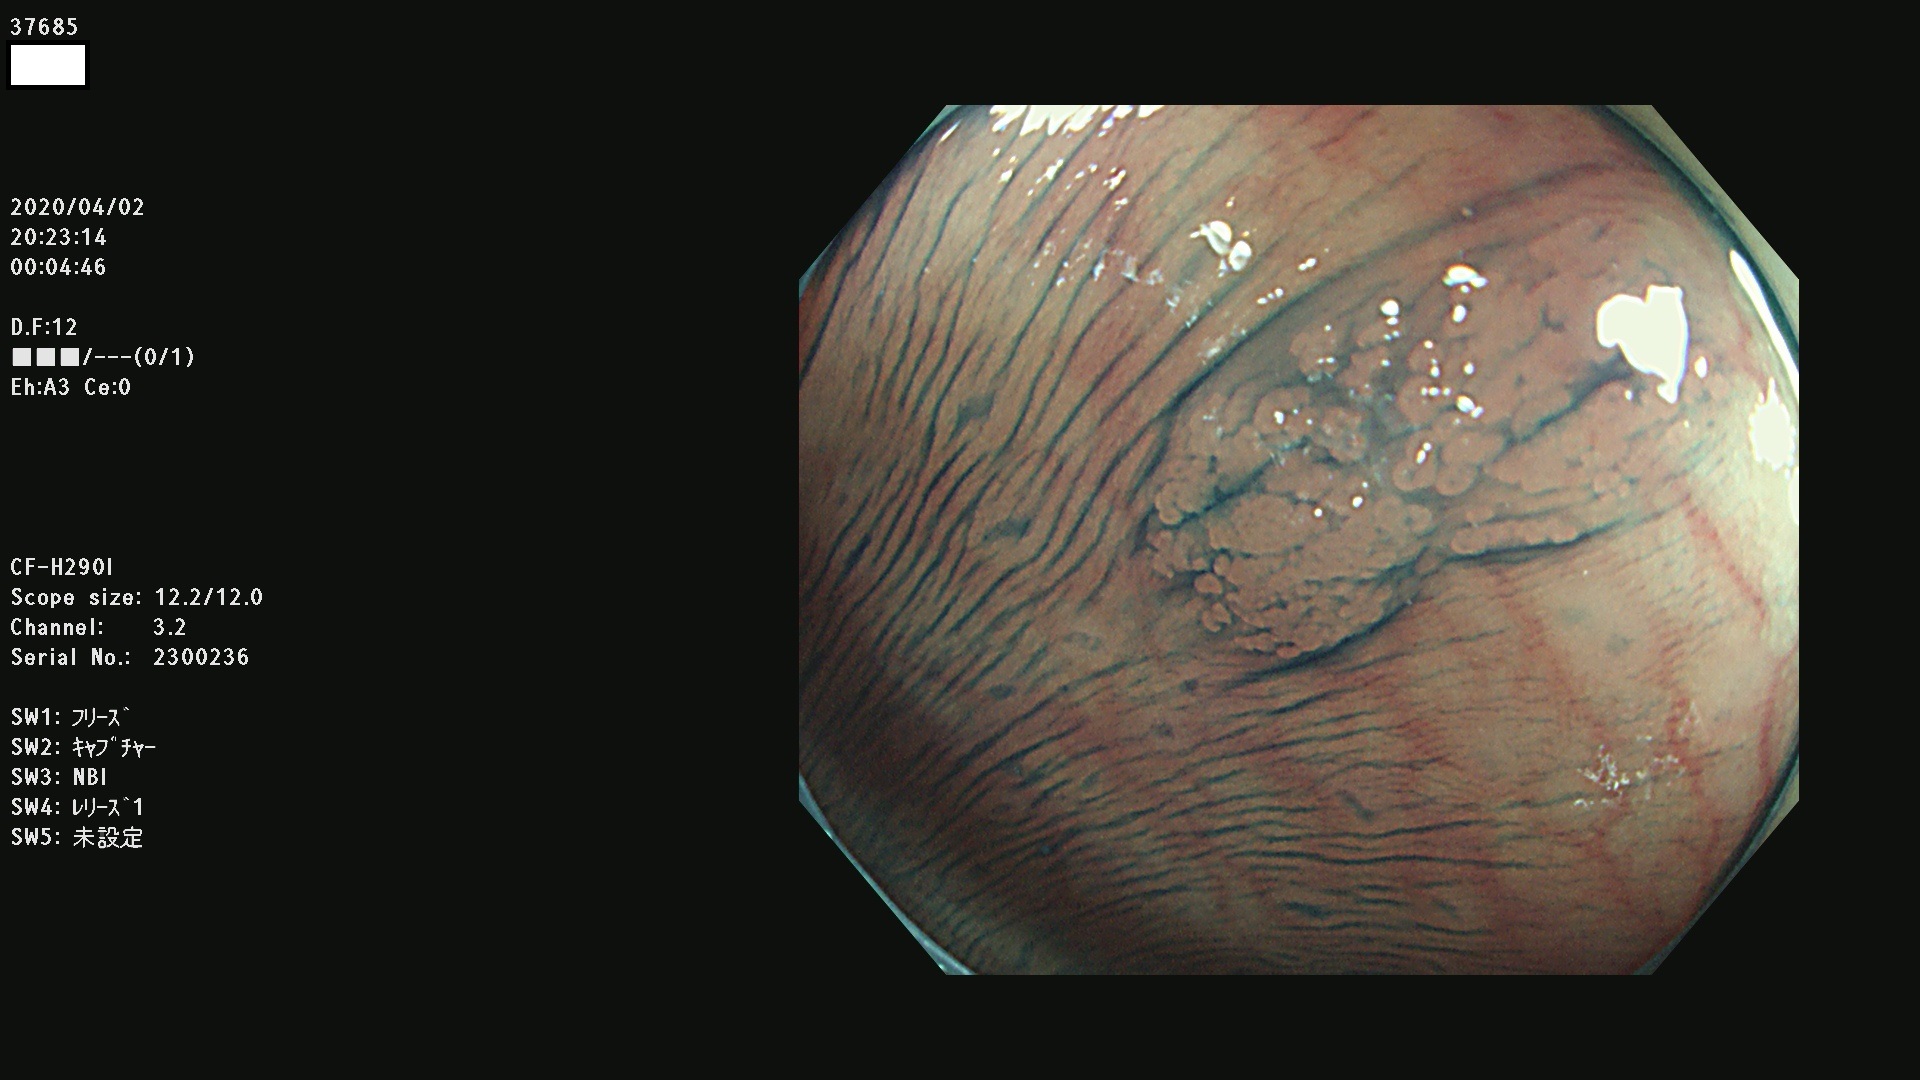

37600 37601 37602 37603 37604 37605 37606 37607 37608 37612 37614 37616 37618 37619 37620 37621 37622(SSAPのみ) 37623(SSAPのみ) 37624 37626 37627 37628 37629 37632 37633 37635 37636(SSAPのみ) 37639 37640 37641 37642 37643 37644 37647(SSAPのみ) 37648 37649 37650 37652 37653 37655 37657 37659 37660 37662 37664 37666 37668(SSAPのみ) 37670 37671 37672 37676 37677 37678 37679 37680 37682 37684 37685(SSAPのみ) 37686 37687 37688 37689 37690 37691 37692(SSAPのみ) 37693 37694 37695 37696 37697 37699

発見困難で危険性の高い平坦型病変(上記100名より抽出)